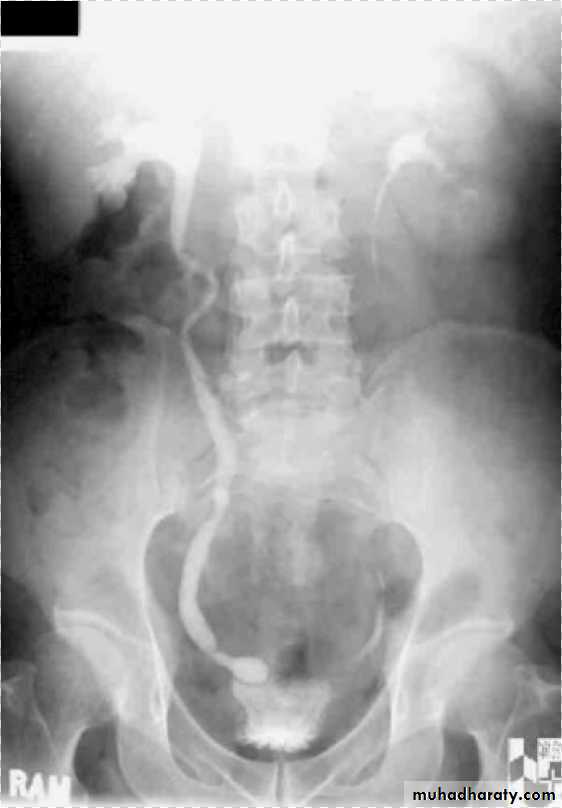

12- Bilateral megaureter